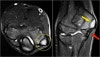

- MRI

There is marrow edema in the medial epicondyle and also in the adjacent bone (yellow arrow).

By the way this could also be called a Salter-Harris type I fracture, if it was an acute traumatic event.

Notice the normal ulnar collateral ligament (red arrow).

In children the weak link in valgus stress is not the ulnar collateral ligament but the physis.

MRI : 야구선수 팔꿈치(Little Leaguer’s Elbow)